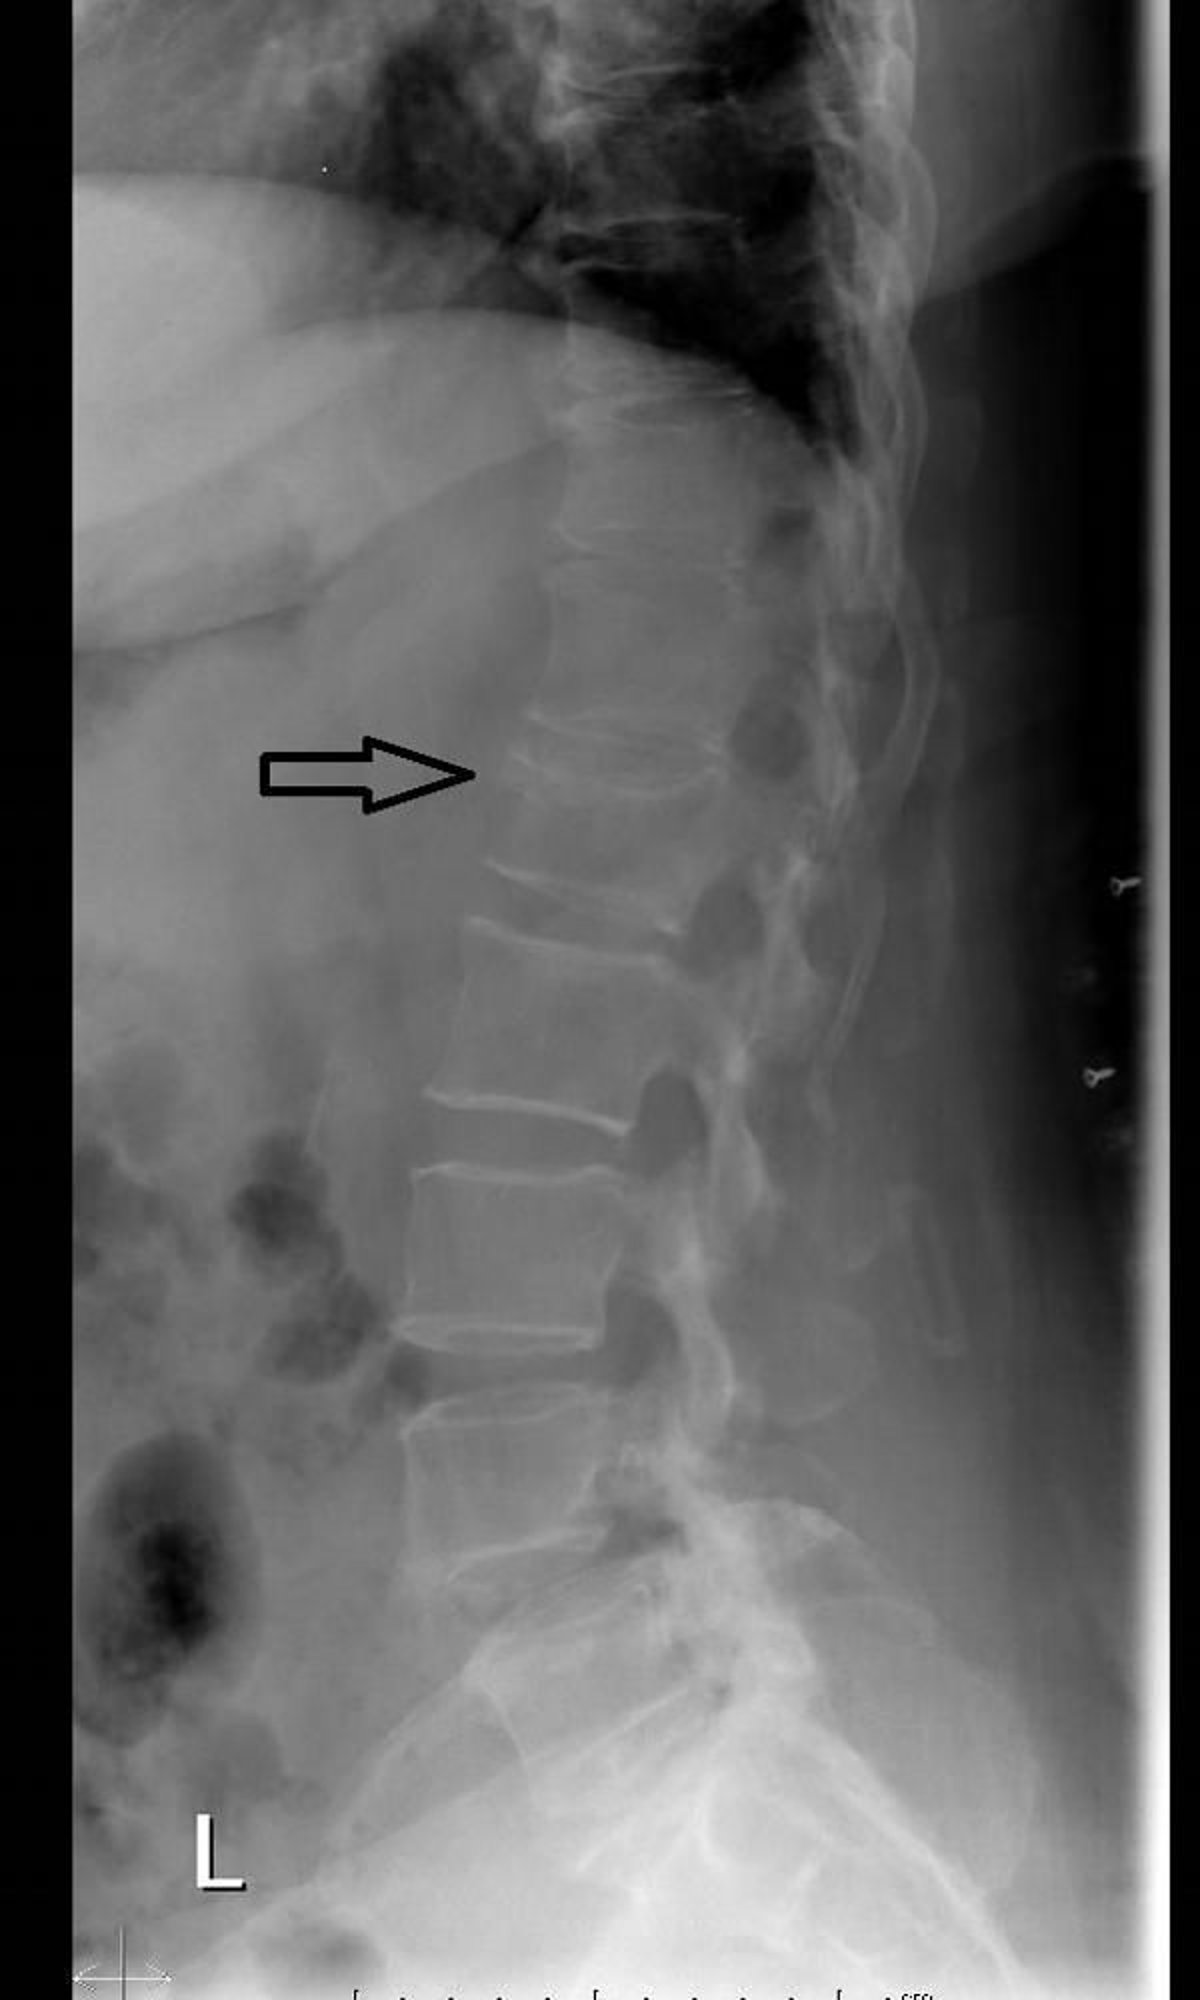

Fracture par compression vertébrale (radiographie)

Cette radiographie de la colonne vertébrale montre une perte de hauteur et la formation d'un coin antérieur en raison d'une fracture vertébrale par compression (tassement).

Image courtoisie de Danielle Campagne, MD.